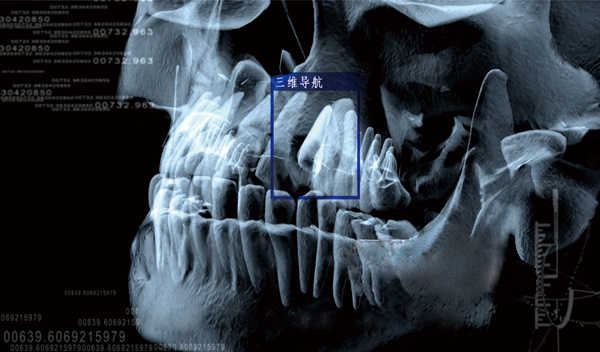

苏州美奥口腔王汉禹院长介绍,计算机三维专业种植导板配合All-on-4即刻负重种植手术,在缩短手术时间,专业定位种植位置,提升种牙安全性上展现了智能科技的专业优势。

▲三维CT口腔影像数据捕获

三维专业种植导板在多颗,半/全口种植中,能在种牙前对牙骨的高度、宽度、深度进行测量并动画模拟真实手术。也就是说在真实手术前,医生就在计算机生成的三维影像上进行了一次种植手术预演,预先标注专业的种植位置,最终制作成一个种植导板。

患者在手术时,将导板佩戴在口腔内,医生可以根据导板上的标注位置确定种植位置,而不是通过传统的人眼目测,大大提高了种植的精确性和降低手术风险,手术时间大幅度缩短,降低了患者的痛苦,条件允许可实现微小切口、不翻瓣、无缝合的手术治疗。

▲三维导板确定种植牙位置